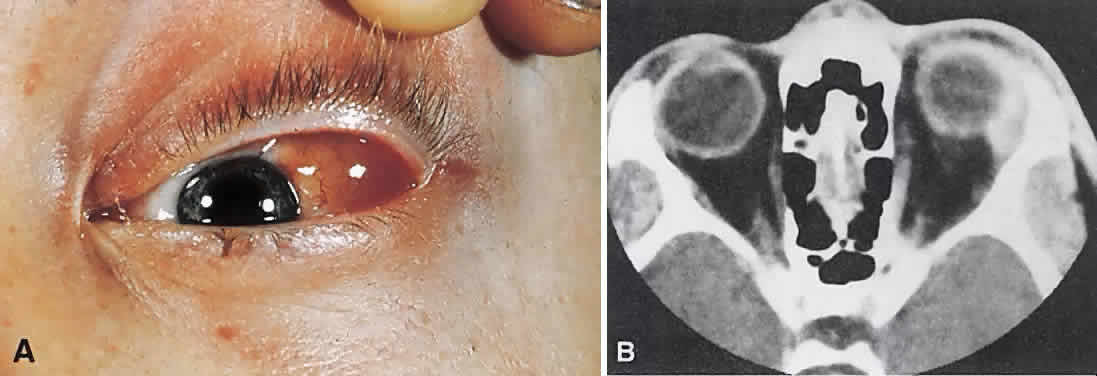

tumor, and diagnostic studies may be required for differentiation.  Fig. 7. A. A 10-month-old girl presenting with an inferior orbital tumor that proved

to be a capillary hemangioma. B. CT of this patient shows an inferior orbital tumor mass that has caused

generalized expansion of the bony orbit, suggesting chronicity. Fig. 7. A. A 10-month-old girl presenting with an inferior orbital tumor that proved

to be a capillary hemangioma. B. CT of this patient shows an inferior orbital tumor mass that has caused

generalized expansion of the bony orbit, suggesting chronicity.

|

CT (see Fig. 7B) shows a homogeneous mass that is not particularly distinct from normal

orbital structures. Depending on the growth rate, there may be enlargement

of the bony orbit in a smooth, symmetric pattern, a nonspecific

finding produced by any lesion that has slowly expanded in the first

few years of life. Capillary hemangiomas are soft, compressible lesions

that grow without indenting the globe. Intravenous contrast agent enhances

the tumor's radiodensity, but this feature does not distinguish

the lesion from malignant tumors that may be in the differential

diagnosis. The high contrast sensitivity of MRI allows better delineation of capillary